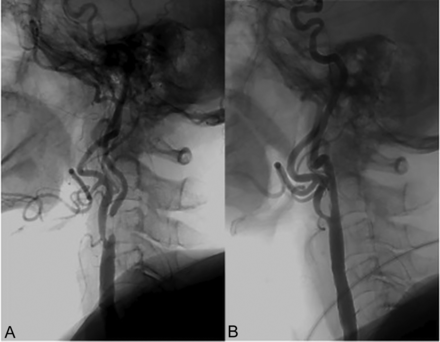

Fifty-eight of the 59 CAS procedures were successful. In 1 case of near-occlusion with collapse, we were not able to pass through the stenosis because of patient motion under conscious sedation; the patient was advised to undergo stent placement under general anesthesia during the procedure, but he refused to have any type of procedure under general anesthesia. Examples of the procedures in 2 patients with and without collapse are provided in Figs 2 and 3. Additional stents were used in 12 of the 58 cases. In 10 cases, the second stent was deployed because the operator’s threshold to deploy a second stent in case of the slightest suspicion of plaque prolapse is low. In 2 cases, the second stent was deployed as the position of the first stent was deemed to be less than ideal by the operator. Overall, 17 patients were asymptomatic, and the permanent morbidity and mortality rate, excluding transient symptoms related to hyperperfusion syndrome, in this group was 0%. One patient of 17 in this group had an episode of a seizure related to hyperperfusion syndrome and was treated with antiepileptics promptly and without any clinical consequences. Forty-one patients were symptomatic. Of these, 1 died as a result of stent occlusion, and 1 had residual hemiparesis after hyperperfusion syndrome, resulting in a permanent morbidity and mortality rate of 4.9%. In this group, 1 patient complained of headache, and head CT revealed minor intracranial hemorrhage (Fig 4). The patient’s initial mRS score was 3 and remained 3 on follow-up.

A and B, Preoperative cervical and cranial angiograms in patient with near-occlusion with collapse (arrow in A), respectively. C and D, Postoperative cervical and cranial angiograms show improvement of diameter of ICA and restoration intracranial blood flow, respectively.

Pre- and postoperative cervical lateral angiograms in patient with near-occlusion without collapse, respectively.